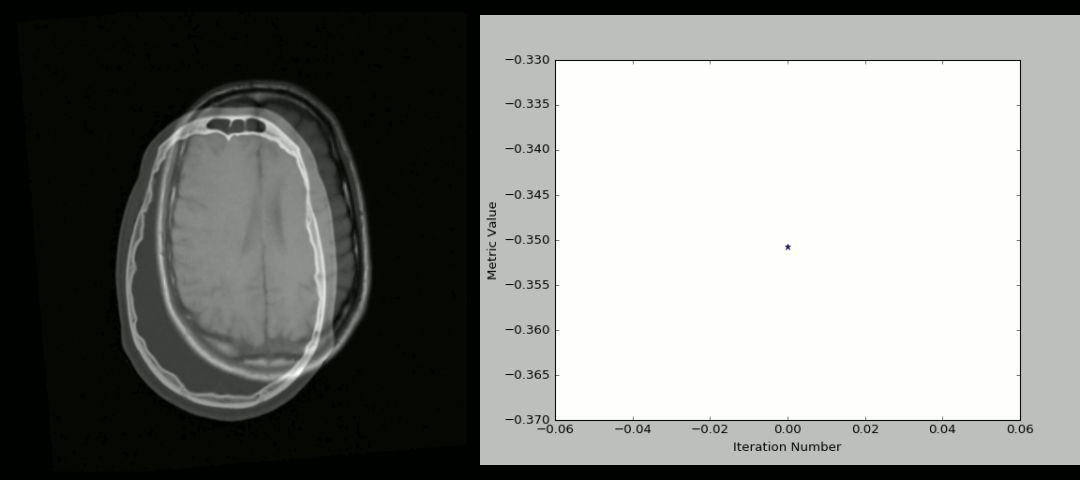

8. SimpleITK

ITK 或者 Insight Segmentation and Registration Toolkit是一个开源的跨平台系统,为开发人员提供了一套广泛的图像分析软件工具 。其中, SimpleITK是建立在ITK之上的简化层,旨在促进其在快速原型设计、教育、解释语言中的应用。SimpleITK 是一个图像分析工具包,包含大量支持一般过滤操作、图像分割和匹配的组件。SimpleITK本身是用C++写的,但是对于包括Python以内的大部分编程语言都是可用的。

用法

下面的动画是用SimpleITK和Python创建的刚性CT/MR匹配过程的可视化 。下面是源码:

https://github.com/InsightSoftwareConsortium/SimpleITK-Notebooks/blob/master/Utilities/intro_animation.py